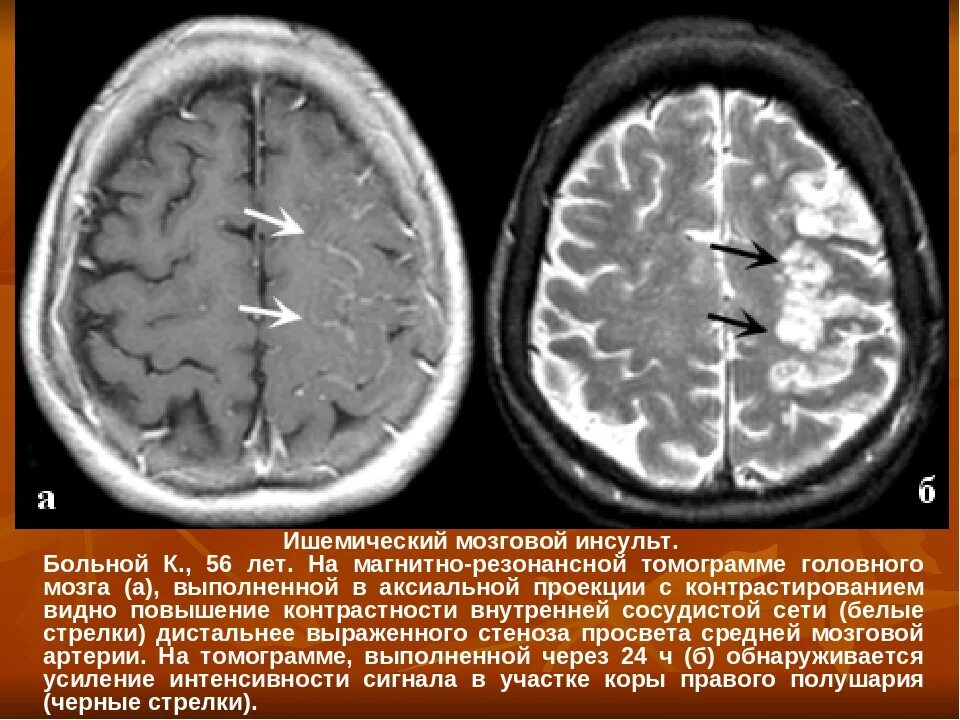

Очаги хронической ишемии головного мозга